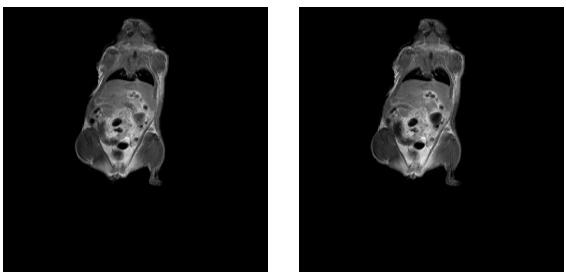

4、核磁共振成像科研性实验样品观察(小鼠,小动植物体等样品的三维、二维成像实验),小鼠分子影像科研实验研究;

肿瘤鼠图片